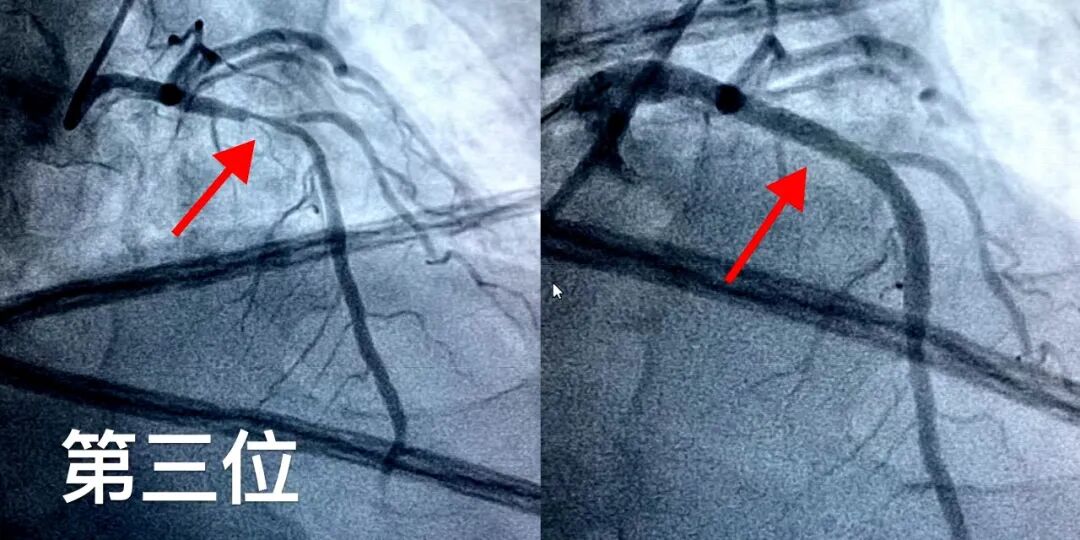

第四位患者为47岁男性,因“颈部不适2小时”来院就诊。这一症状并非典型胸痛,极易被忽视或误诊。但接诊医生保持高度警惕,经快速评估后行冠脉造影,明确为回旋支病变导致的心梗,并成功实施急诊PCI开通血管。